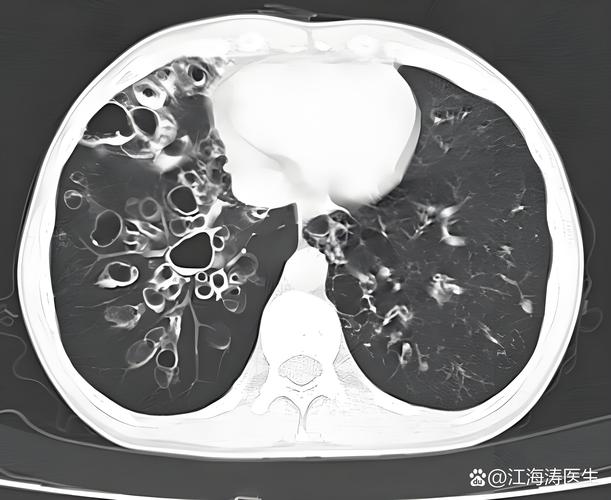

(图片来源网络,侵删)